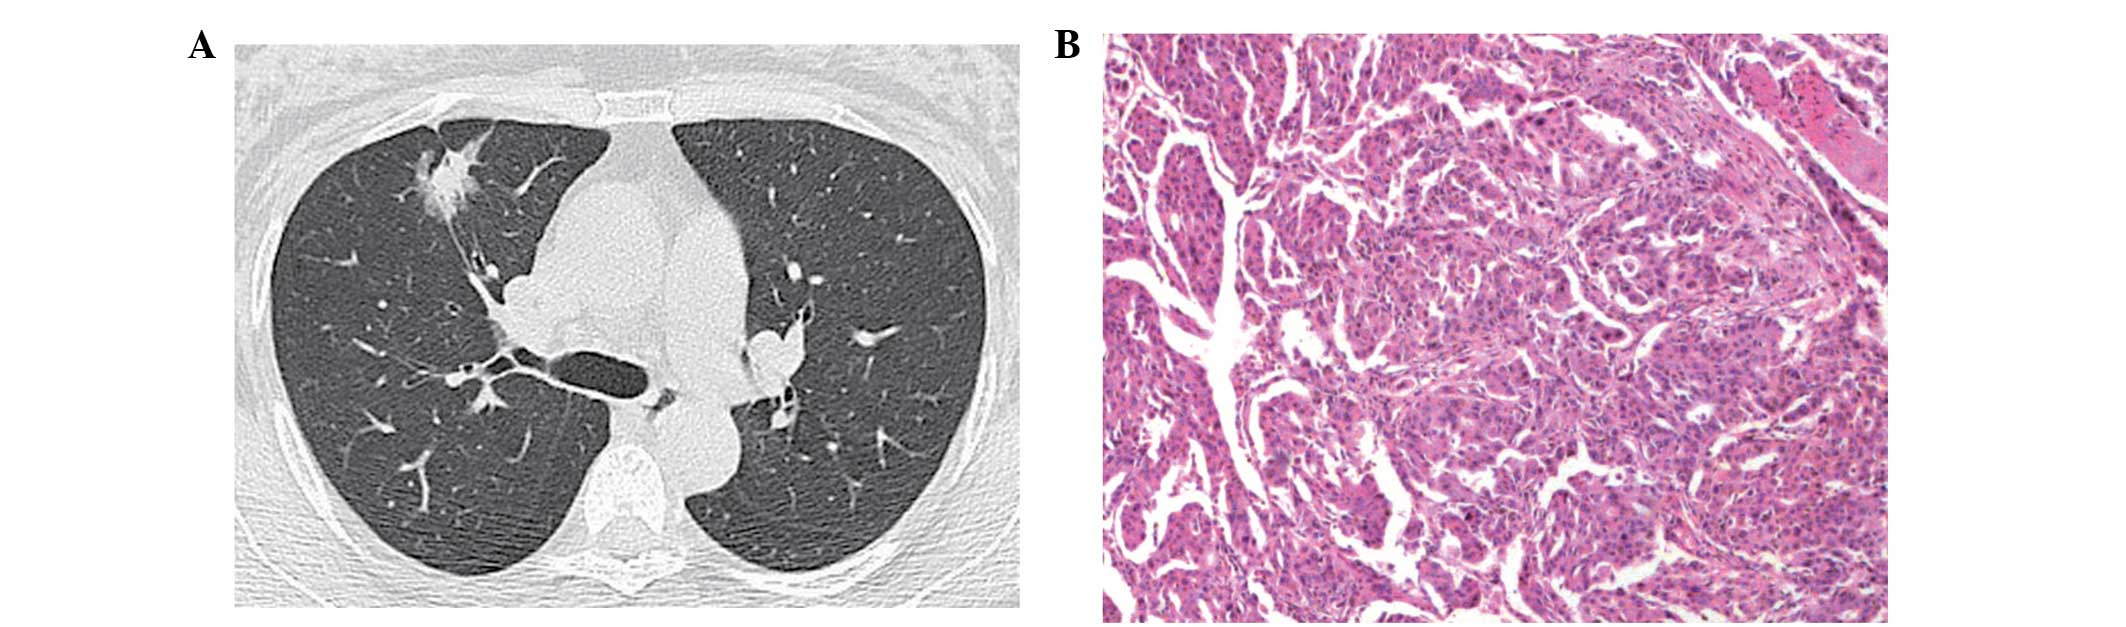

(A) Computed tomography image showing a tumor with pure ground-glass opacity, without obscuring the underlying vascular structures. (B) Lesion was diagnosed as a adenocarcinoma in situ (hematoxylin and eosin stain; magnification, x200). The findings were negative for epidermal growth factor receptor and Kirsten rat sarcoma mutations.